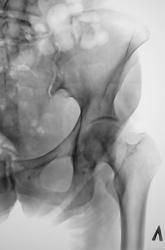

Газовая атака какая-то. Костная структура головок неоднородная, болье слева, а "преклонный" возраст может быть связан с остеопорозом и кистовидными просветлениями. А по поводу чего ее обследуют-коксартроз, новообразования и тд?

Вот мы и нашли: газ и содержимое толстой кишки.

Единственная зацепка. Остальное - по возрасту и кишкам. Ну и сноска на укладочку допустима у старушек.

Я бы не стал все списывать на газ. Многие просветления в костях подозрительны на остеолитические метастазы.

Пациентке животик бандажиком поприжать и сделать косые снимочки, снимая/подтверждая подозрения всех участников художественного марафона.